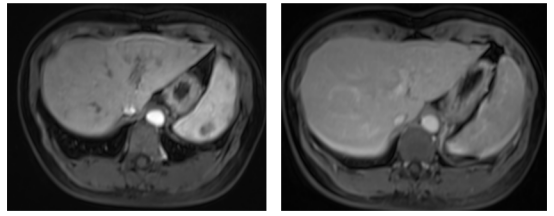

患者在2010年3月-11月,接受了伊尼妥单抗联合长春瑞滨治疗8周期后,采用伊尼妥单抗单药维持治疗4周期。结果评估显示:上腹部MR增强:肝内转移灶治疗后改变,无肿瘤活性;胸部增强CT及骨ECT均未见异常,患者后续随访,至今疾病无进展,可谓痊愈。

(2020-9-21上腹部MR增强:肝内转移灶治疗后改变,无肿瘤活性;胸部增强CT及骨ECT均未见异常。)